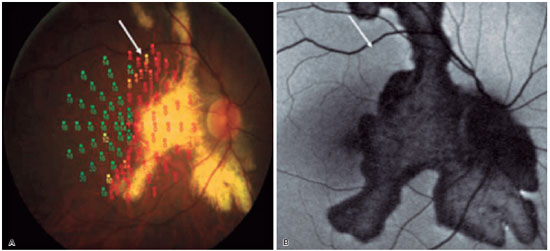

Figure 7. Retinal sensitivity and autofluorescence in a patient with inactive serpiginous choroiditis. (A) Area with white arrow with partial reduction in sensitivity. (B) White arrow shows the same corresponding area showing normal autofluorescence and no serpiginous lesion at the site. (Source: Pilotto, E et al. Retinal function in patients with serpiginous choroiditis: a microperimetry study. Graefe's Archive for Clinical and Experimental Ophthalmology; 2010, 248(9), 1331–1337)8.